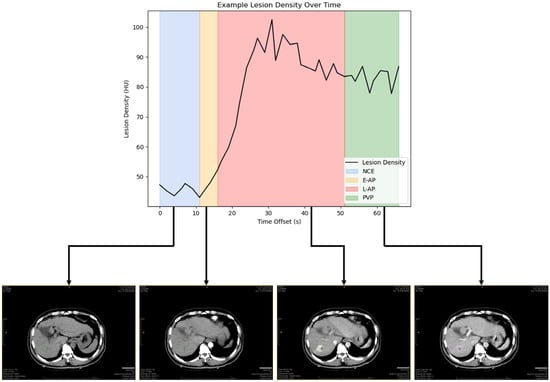

2.2. Reference Standard for Contrast Enhancement Phases

2.3. Lesion Segmentation and Measurements

| Phase | Coefficient of Variance (CV) | Standard Deviation (HU) | Example Tumor | ||

|---|---|---|---|---|---|

| Mean Density (HU) | Range as a Result of Variability (HU) | % Change as a Result of Variability | |||

| All | 26.19% (24.66–27.72%) | 15.57 | 76.41 | 34.8–118.0 | ±54 |

| NCE | 9.62% (7.15–12.09%) | 9.73 | 45.03 | 36.4–53.6 | ±19 |

| E-AP | 7.58% (6.08–9.09%) | 10.59 | 44.25 | 37.1–51.5 | ±16 |

| L-AP | 22.84% (21.48–24.20%) | 18.93 | 77.96 | 41.6–114.4 | ±47 |

| PVP | 7.83% (6.76–8.89%) | 16.68 | 88.01 | 73.6–102.4 | ±16 |